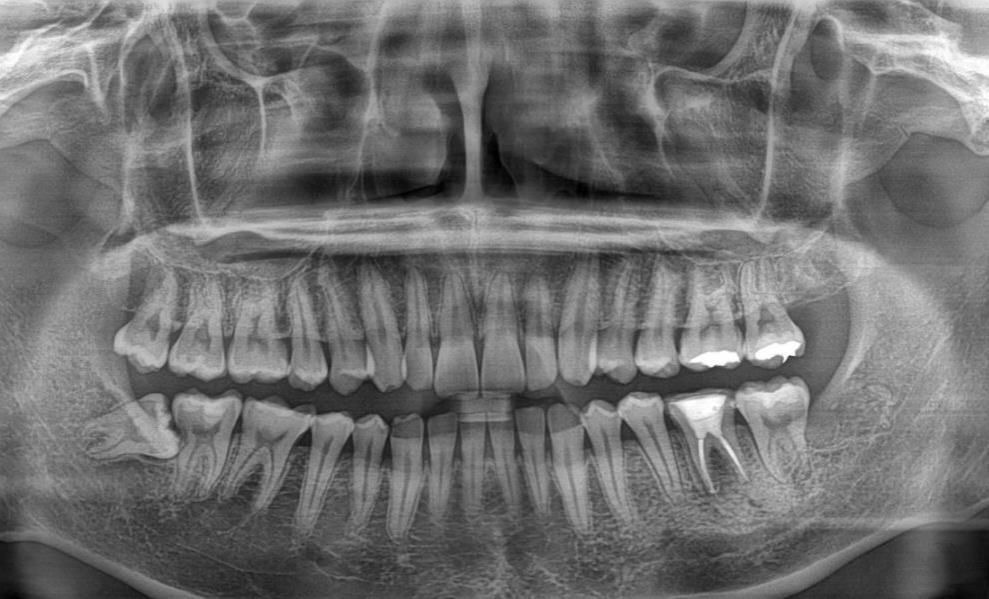

첫번째 사진은 사랑니 발치전(06.11)에 찍은 파노라마 사진입니다.

Q1. 두번째 사진에서 보면 신경치료 한 치아(오른쪽 하단 어금니) 왼쪽 뿌리쪽에 신경치료한 약재가 두갈래로 갈라져있습니다.

반면 첫번째 사진에서는 파노라마상 약재가 갈라져있는게 보이지 않는데 무슨 문제가 생긴 것인가요?

Q2. 2번째 사진에서 신경치료 받은치아 오른쪽 치아 인대쪽에서 검은색 염증같이 무언가 보입니다. 염증일까요?

엑스레이 촬영에 따라서 근관 2개가 겹쳐 보이는경우가 잇고 나눠져 보이는 경우 인거 같습니다.

뿌리 끝에 있는 재료의 형태는 사진을 찍는 각도에 따라 다르게 보이기도 합니다.

1. 약재가 아니고 gp cone이라는 충전재이며 어금니는 신경관이 근심에 2개, 원심에 1~2개 있습니다 근심 2개의 신경관이 첫번째 엑스레이에서는 중첩되어 있고, 두번째 사진에선 각도가 잘 나와서 2개다 보이는 겁니다

2. 원심쪽 뿌리에 염증 양상이 있어보이긴 합니다